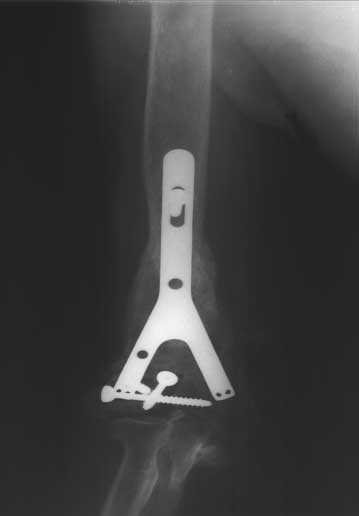

肱骨远段骨折,骨缺损。多次手术失败      准备植入的大块异体骨13厘米长,采用Y型钢板固定

恢复上肢长度,大块异体骨植骨修复骨缺损、Y型钢板固定     术后X线片,显示骨缺损已经愈合